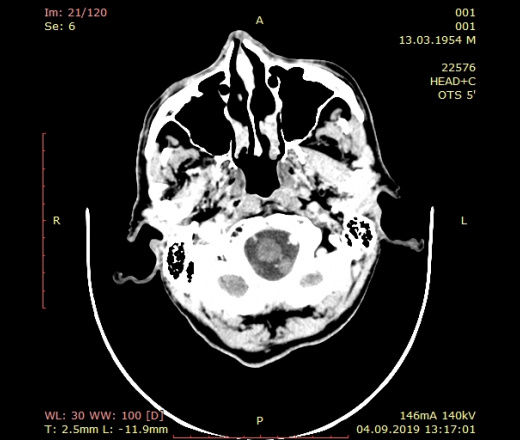

М, 65 лет. Поступил в стационар на диф.диагностику легочного туберкулеза. Появились неврологическая смиптоматика, было выполнено КТ ГМ С контрастом. Там такая картина. Голову не пишу и о чем думать не представляю, как это описывать тоже. Нужны авторитеные мнения и ссылки на литературу, буду благодарен любой помощи. Ссылка на исследование целиком: https://drive.google.com/drive/folders/1fRknkK43mmVZlLgnZi1mLx-Ykvgy_1Be?usp=sharing

Итак, к глубоком белом веществе правого полушария мозга есть малое,  накапливаюшее контраст, образование с  большой зоной перифокального отека. Высказался бы за метастаз. В левом полушарии - вероятна постинфарктная киста. Дайкомы не смог посмотреть, там какая-то непонятка с Гугл-диском.

Справа опухоль с выраженным отёком преимущественно по белому веществу вокруг, слева состояние после перенесенного инфаркта..

И еще небольшой вопрос.Невролог выставил энцефаломиелит под вопросом, почитал в доступной литературе, что тоже зона гиподенсная, накапливаящая контраст, с перифокальным отеком. Можно написать в диф.ряд или не стоит?